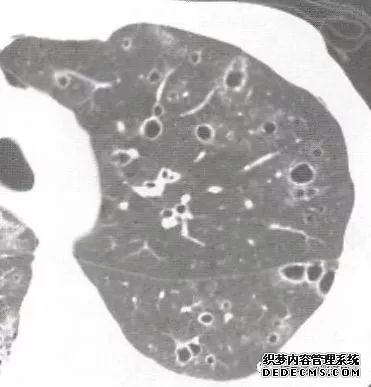

肺转移瘤的十种不典型CT表现